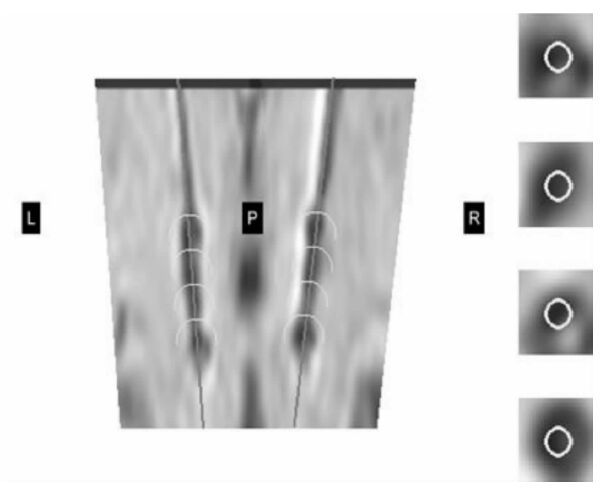

最后,在冠狀圖上檢測自動選定的觸點位置是否準確,再進一步精確調整電極觸點的位置,如圖 4所示,其中R代表腦右側,L代表腦左側,P代表腦后側。如果電極觸點位置有偏差,就沿電極路徑上下調整觸點位置,從而得到包含電極觸點位置的完整電極植入信息。所有觸點都是同時移動的,保證了電極觸點間距相等。

在標準化術中影像的基礎上,自動重建電極植入路徑,用術中的冠狀圖像校驗重建的電極路徑,如圖 4所示,可以精確調整路徑方向,以及電極觸點位置。